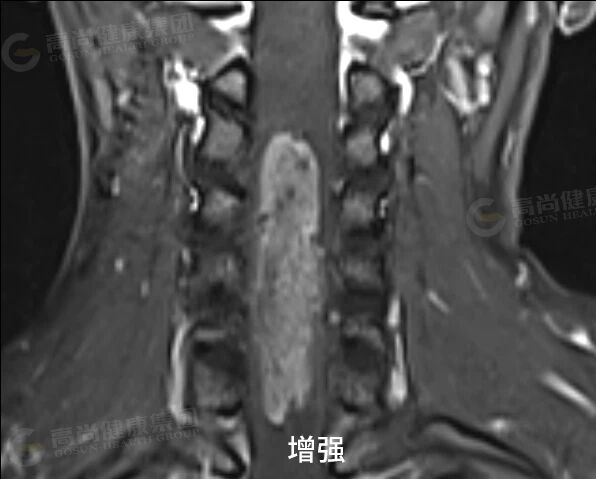

女性,34 岁,外院诊断脊髓空洞,走路失稳伴肢体麻木,来中心增强检查。

延髓水平至 T12 椎体水平椎管内可见分布大小不等囊状信号,C2 椎体下缘水平至 C7 椎体水平下缘髓内可见长 T1、混杂长 T2 信号,病灶两端见弧形低信号,T2 压脂示病灶内散在结节状稍高信号,横轴位见肿块位于脊髓中央,正常脊髓显示不清,增强扫描呈轻中度不均匀强化,范围约 73 mm×15 mm。

结论:颈髓内占位伴广泛性脊髓囊样改变,考虑室管膜瘤伴脊髓空洞可能。

增强扫描特征: 绝大多数(>95%)室管膜瘤明显强化。强化模式多样:可呈均匀、不均匀或环状强化。强化边界通常清晰,有助于划定肿瘤范围。